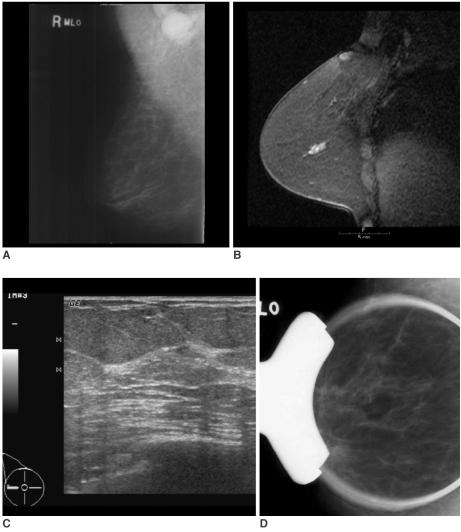

MR imaging detected occult breast carcinoma in 10 of 12 (83%) patients. Two MR-negative patients were free of carcinoma in the ipsilateral breast during their follow-up period (39 and 44 months, respectively). In nine out of 10 patients, the MR-correlated mammography and second-look sonography localized lesions that were not detected on the initial exam. All the non-MR-correlated sonographic abnormalities were benign.

Breast MR imaging can identify otherwise occult breast cancer in patients with metastatic axillary lymph nodes. Localization of the lesions through MR-correlated mammography and second-look sonography is practically feasible in most cases.